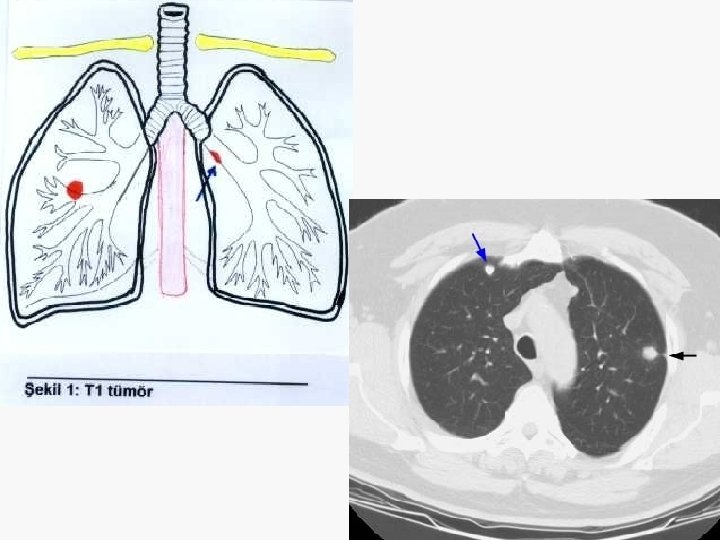

5. 4 cm

Evreleme EVRE 0 : Tis N 0 M 0 EVRE IA : T 1 N 0 M 0 EVRE IB : T 2 N 0 M 0 EVRE IIA : T 1 N 1 M 0 EVRE IIB : T 2 N 1 M 0 T 3 N 0 M 0 EVRE IIIA : T 1 -3 N 2 M 0 T 3 N 1 M 0 EVRE IIIB : T 4 N M 0 T N 3 M 0 EVRE IV : T N M 1